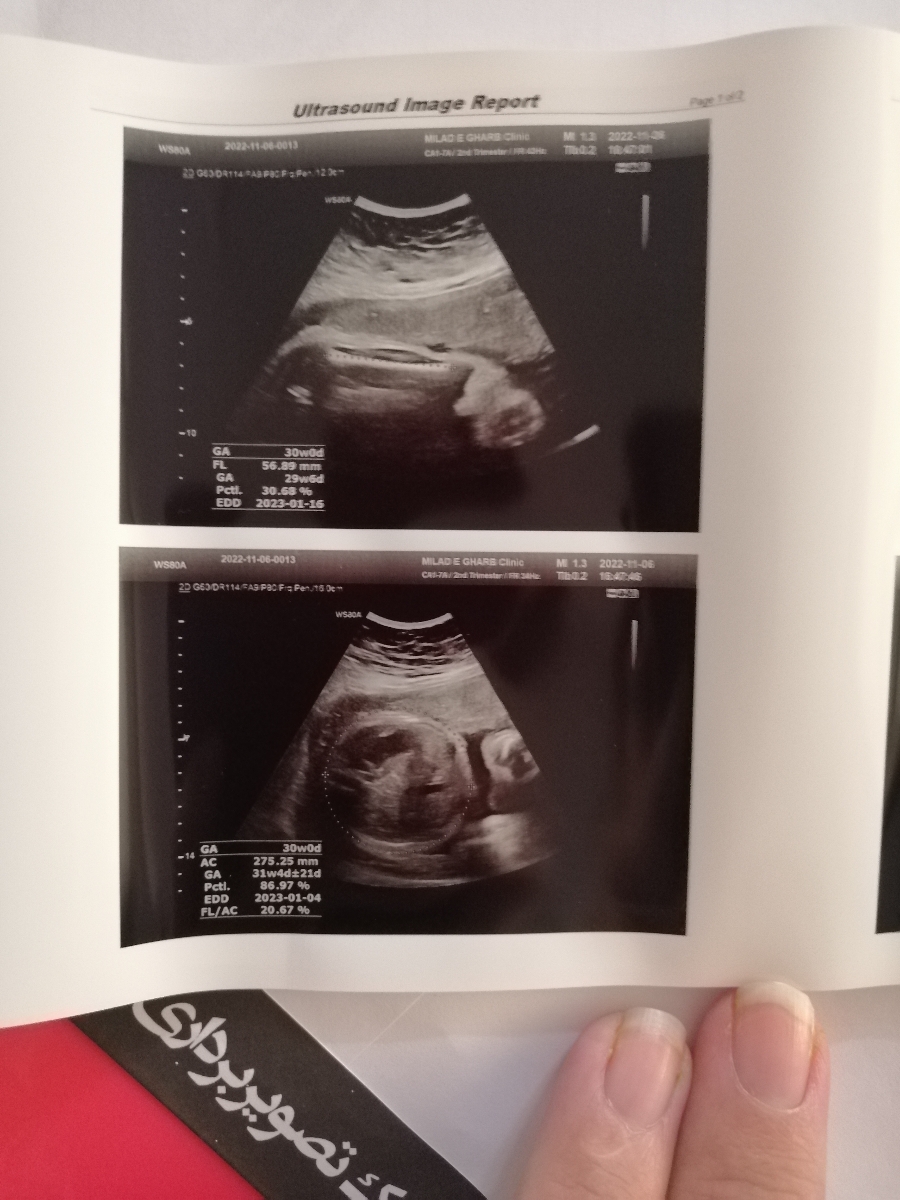

امکان داره با توجه به عکسی که ارسال میشه تاریخ زایمان رو به من اعلام کنید چون تو برگه سونو که دبرور انجام دادم تاریخ نزده بود

تاریخ زایمان چندم میشه؟

تاریخ زایمانت میشه 1401/10/13

توی عکس اون قسمت که نوشته EDD2023-01-03 میشه تاریخ زایمانت

عزیز تاریخ زایمانو از ان تی میگن.اینا بر اساس رشد بچست .چون این تاریخ ممکنه یکی بچش درشت باشه جلوتر باشه یکی لاغرباشه دیرتر باشه

تعیین زمان زایمان بر اساس اولین روز آخرین قاعدگی و سونوگرافی ان تی است، سونوگرافی های بعدی اعتبار کافی ندارند ❤️